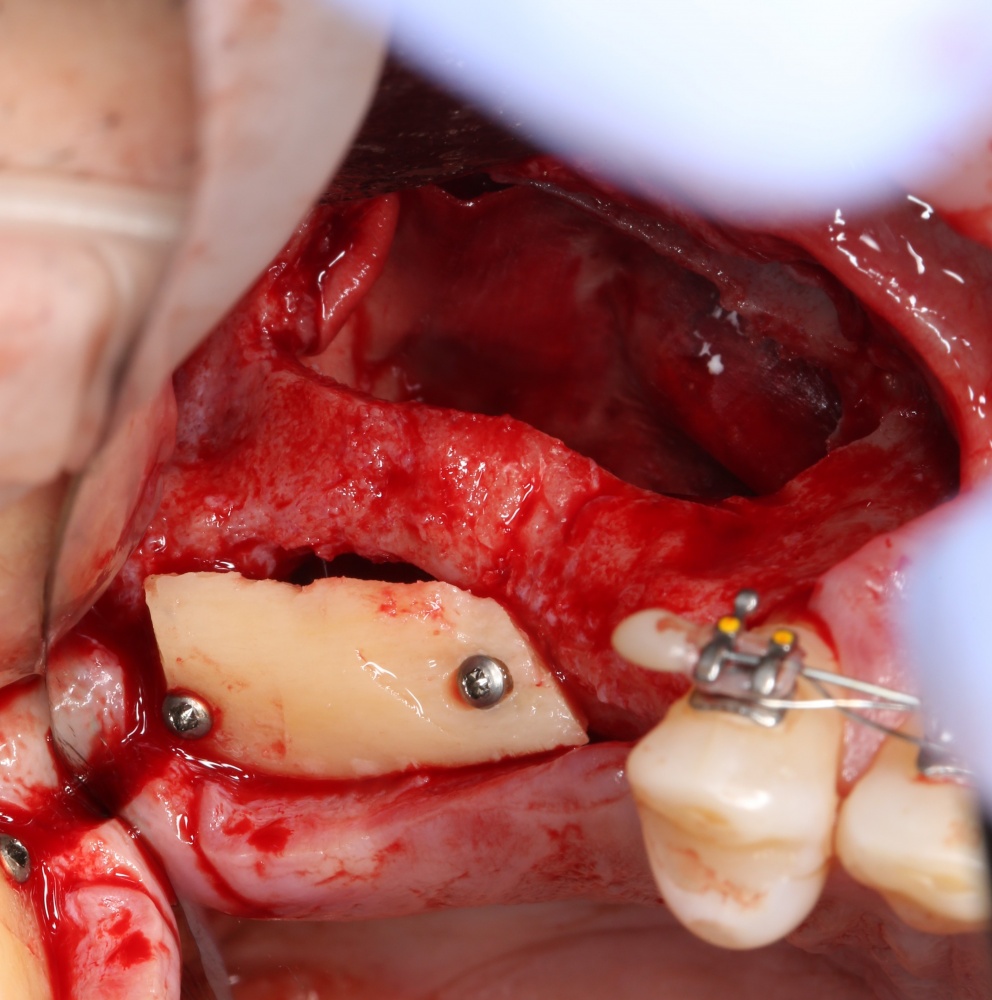

Возвращаемся к основной операционной области. Еще раз посмотрим на альвеолярный гребень, поофигеваем от его ширины и моих грандиозных планов:

Я зафиксировал костный блок практически без адаптации на несколько винтов. Обрати внимание, что винты находятся в зоне, где не планируется установка имплантатов. Фиксация должна быть надежной, поскольку мне еще предстояла подготовка лунок для имплантатов. Трех винтов для этого вполне достаточно.

Дальнейшая адаптация костного блока свелась к сглаживанию острых краев. После чего я приступил к подготовке лунок и установке имплантатов.

Установка имплантатов.

Напомню, что для этой работы я выбрал субкрестальные имплантаты Ankylos C/X. Они прекрасно сочетаются с любым методом остеопластики.

Я не планирую установку супраструктур или коронок, поэтому на уровень первичной стабильности можно положить болт. Даже наоборот — чем меньше крутящий момент при установке, тем лучше. Для имплантатов Ankylos и подобных им, это особенно важно. В общем, момент силы при установке — не более 10-15 Нсм.

Ремарка: имплантаты с предустановленными имплантодержателями хороши тем, что с ними легко контролировать позиционирование имплантатов. В случае с Ankylos С/Х - еще и крутящий момент. Имплантодержатель должен отсоединяться от имплантата с легким щелчком. Если его клинит, и тебе приходится прикладывать для этого усилия, то ты, однозначно, превысил момент силы во время установки имплантата. Следовательно, жди проблем.

Глянем на то, что получилось:

Осталось адаптировать костный блок (убрать острые края), проверить его фиксацию и, при необходимости, добавить винты. Десятисекундное дело.